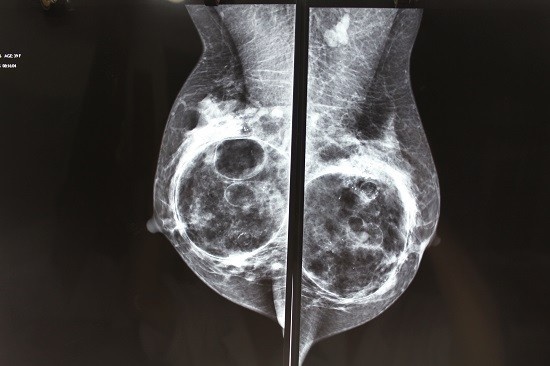

tinh huong nguy hiem khi nang nguc anh 1

Tuyến vú bị biến dạng do nâng ngực bằng chất làm đầy. Ảnh: Bác sĩ cung cấp.